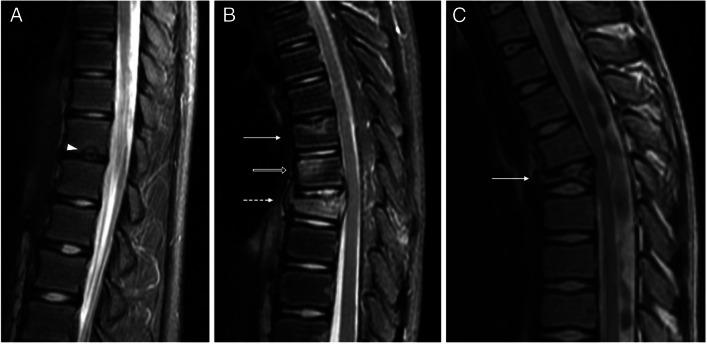

We included 13 patients (six male). The mean age of onset was 12.3 years. Ten patients had only vertebral lesions, two had only mandibular lesions, and one had both. For patients with vertebral lesions, the median number of levels affected was three, 81.8% had multiple levels affected, 90.0% had dorsal spine lesions, 72.7% had platyspondyly, and 81.8% had inflammatory changes. All vertebral lesions had at least partial resolution of inflammatory findings, the mean time of lesion activity was 2.5 years, and recurrence occurred in 27.3%. Three patients had sacral lesions, all with sacroiliitis. In patients with mandibular lesions, all had unilateral lesions involving the mandibular ramus, all had hyperostosis, periosteal reaction, bone edema, and soft tissue inflammation, all had partial resolution on follow-up, and one had recurrence.

CNO vertebral lesions are not rare, are often multiple, predominantly affect dorsal levels, and most result in vertebral height loss. Resolution of vertebral inflammatory lesions is frequent, but so is recurrence. Sacral lesions may be present and result in sacroiliitis. The mandible may be a site of unifocal disease, typically affecting the ramus, with prominent bony changes and soft tissue inflammation.

共纳入 13 例患者(男 6 例),平均发病年龄为 12.3 岁。10 例患者仅存在脊柱病变,2 例仅存在下颌病变,1 例同时存在两种病变。存在脊柱病变的患者中,受累椎体数中位数为 3 个,81.8%的患者存在多个椎体受累,90.0%的患者病变位于胸椎,72.7%的患者存在扁平椎,81.8%的患者存在炎症改变。所有脊柱病变均有不同程度的炎症改变缓解,病变活动的平均时间为 2.5 年,27.3%的患者复发。3 例患者存在骶骨病变,均伴有骶髂关节炎。存在下颌病变的患者中,病变均位于下颌骨升支,均表现为骨增生、骨膜反应、骨水肿和软组织炎症,随访时均有不同程度的缓解,1 例复发。

CNO 的脊柱病变并不罕见,常为多发病变,主要累及胸椎,且多导致椎体高度丢失。脊柱炎症性病变常可缓解,但也易复发。骶骨可能受累,导致骶髂关节炎。下颌可能为单发病变的部位,典型表现为升支受累,有明显的骨改变和软组织炎症。